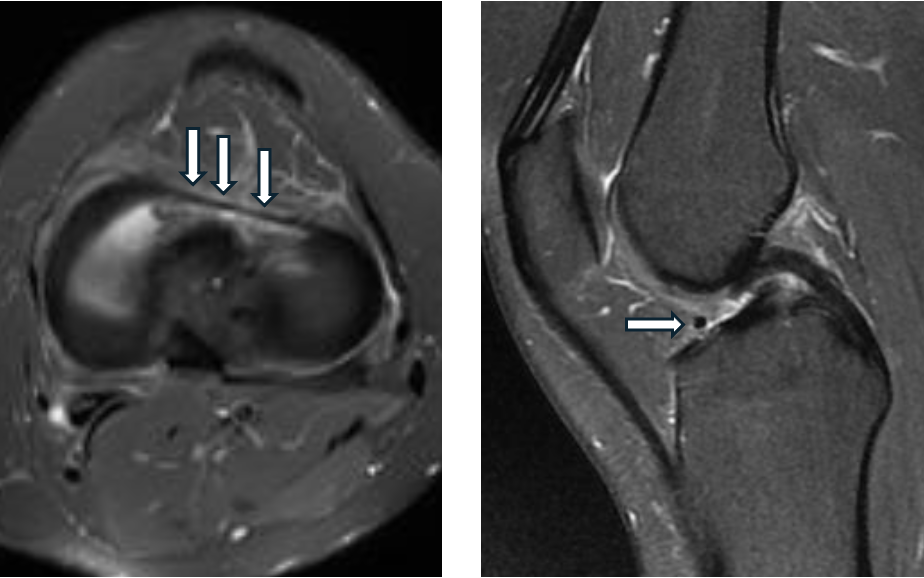

Welche Normvariante ist auf dem vorliegenden axialen und sagittalen PD-fs MRT-Bildern eines Knies mit Pfeilen gekennzeichnet?